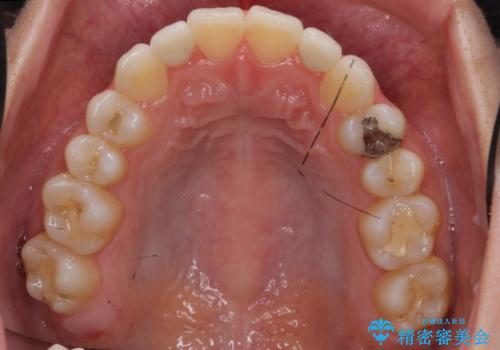

前から2番目の歯が小さく、細くとがった形になっていました。

大きくしようにも、幅が少ない上に、また、内側に入ってしまっているため、矯正治療で前歯を並べてからセラミックでかぶせることにしました。

いきなりセラミックでかぶせるよりも手間をかけた分、自然な仕上がりになっています。

先に矯正治療をすることで、下の前歯を内側に入れることができ、上の歯のセラミックの幅や厚みを取ることができました。